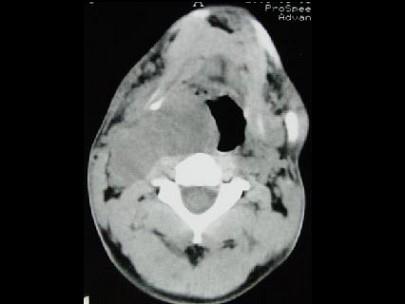

问题 男,41岁,右侧咽部不适两年余,有异物感,声音嘶哑,CT如图所示,最可能诊断为 ( )

选项 A、小唾液腺瘤 B、咽旁神经鞘膜瘤 C、咽旁转移癌 D、咽旁淋巴瘤 E、颈动脉体瘤

答案 B